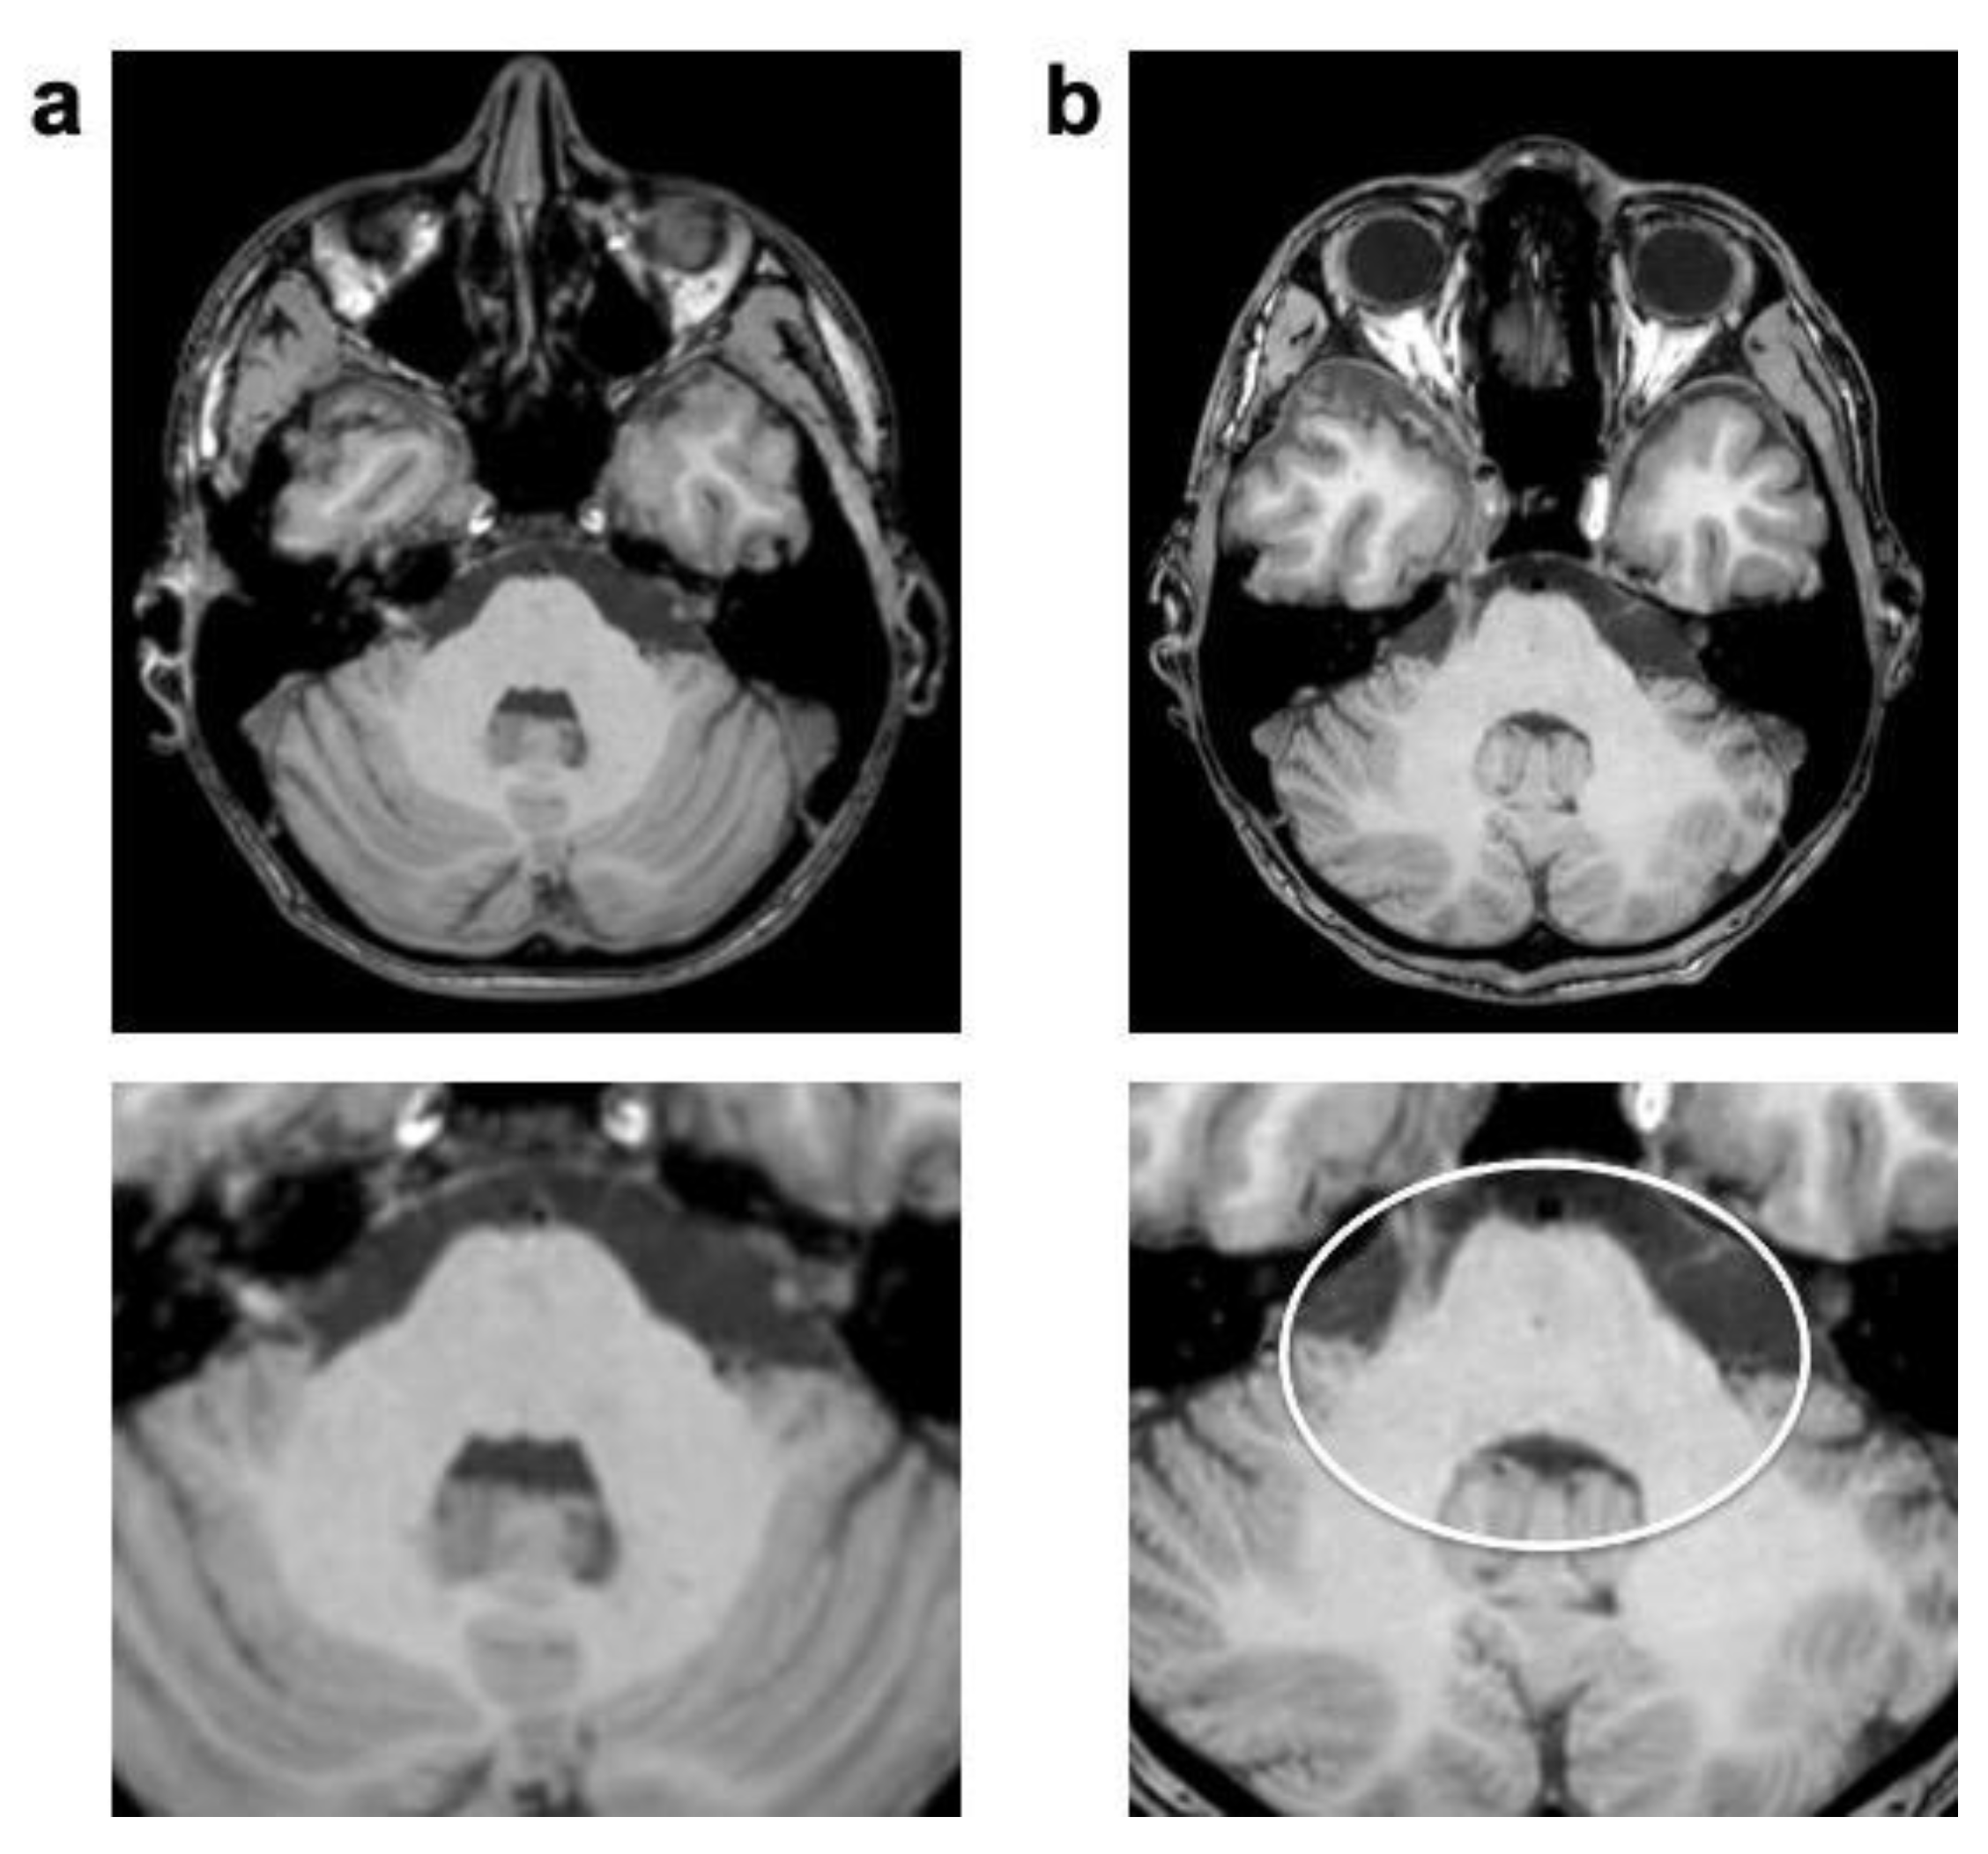

| CSF flow | 22 (100%) | 38 (1.73 ± 0.46) | 22 (100%) | 41 (1.86 ± 0.35) | 0.080 | |

| Pulsation/ghosting | 17 (77% | 22 (1.00 ± 0.69) | 20 (91%) | 26 (1.18 ± 0.59) | 0.041 | |

| Overall | 4.55 ± 1.53 | 4.82 ± 1.10 * | 0.018 | |||